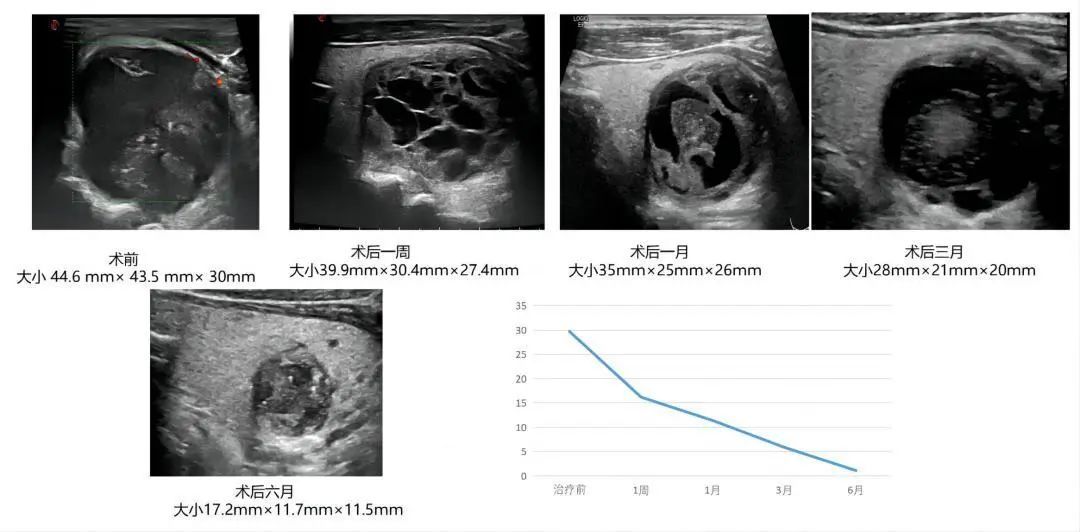

66岁老年男性,甲状腺囊肿硬化治疗后6个月,囊肿大小从30ml缩小到1ml左右,颈部“包块”明显消失。